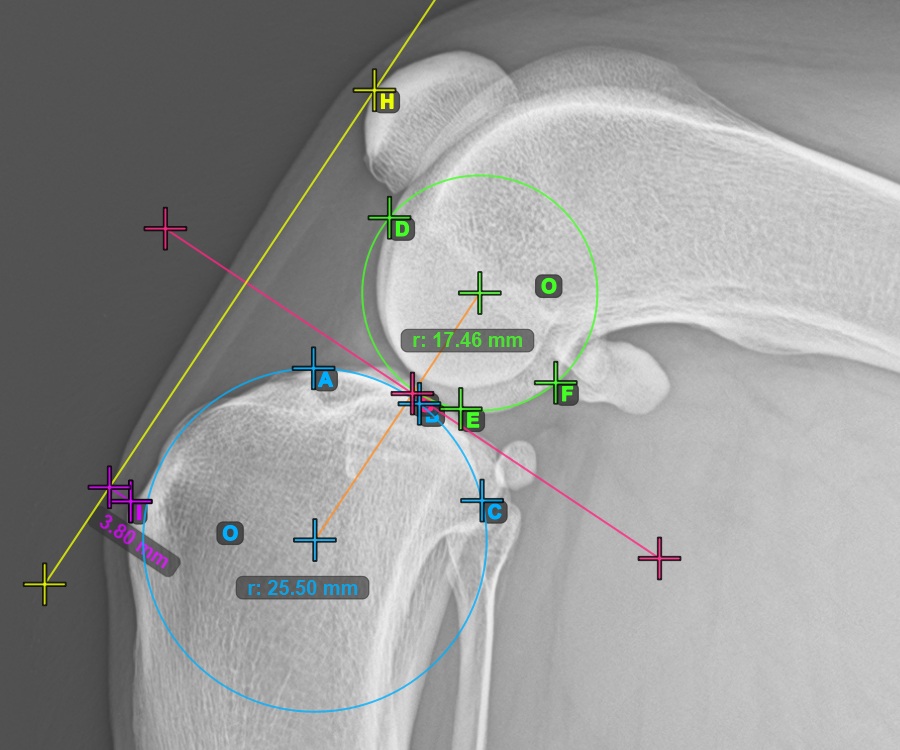

Mark one point in front of the joint on the common tangent between the two circles. A line will be drawn automatically through the marked point.

The image below represents a typical placement of the point on the common tangent between the two circles.

Start the TTA measurement procedure by marking the most cranial point of the Patella.

The image below depicts the usual placement of the most cranial point of the Patella.